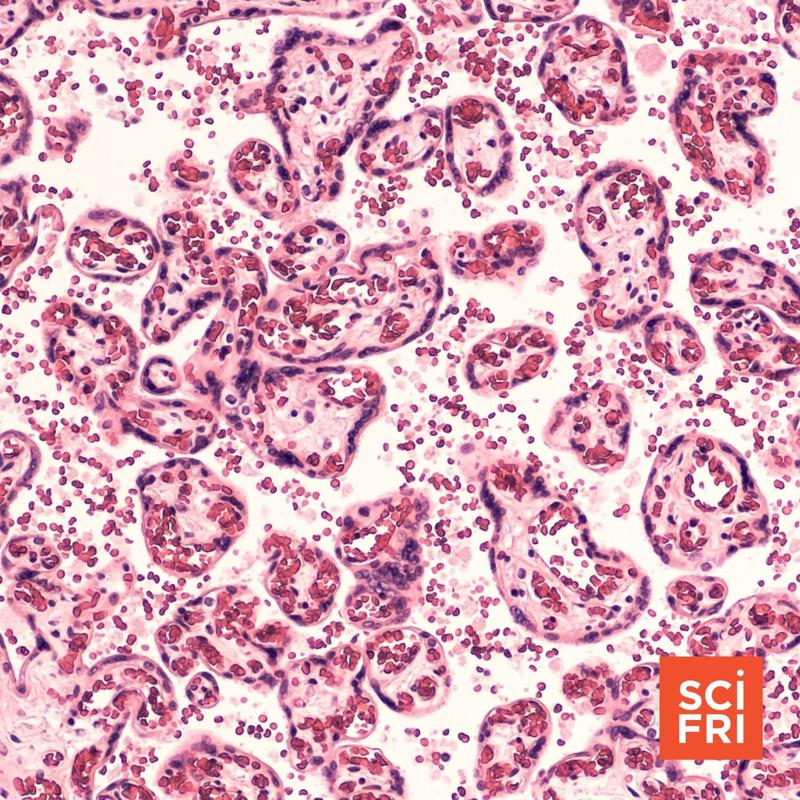

Placenta Research May Help Explain Pregnancy Loss